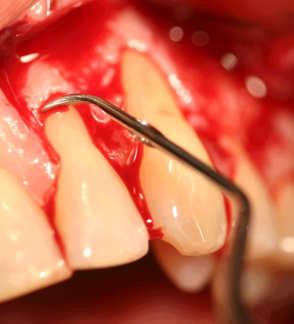

After the flap- opening, follows a careful cleaning of the root surface